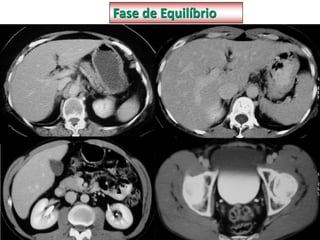

FASE EQUILÍBRIO

• Contraste sai dos vasos para o parênquima

tissular

• Cortes de 1mm

• Débito de 2ml/s bomba injetora

• Delay 3-7 minutos

• Permite a avaliação de vários tumores

• Avaliação do sistema coletor do aparelho

urinário.

Fase de equilíbrio